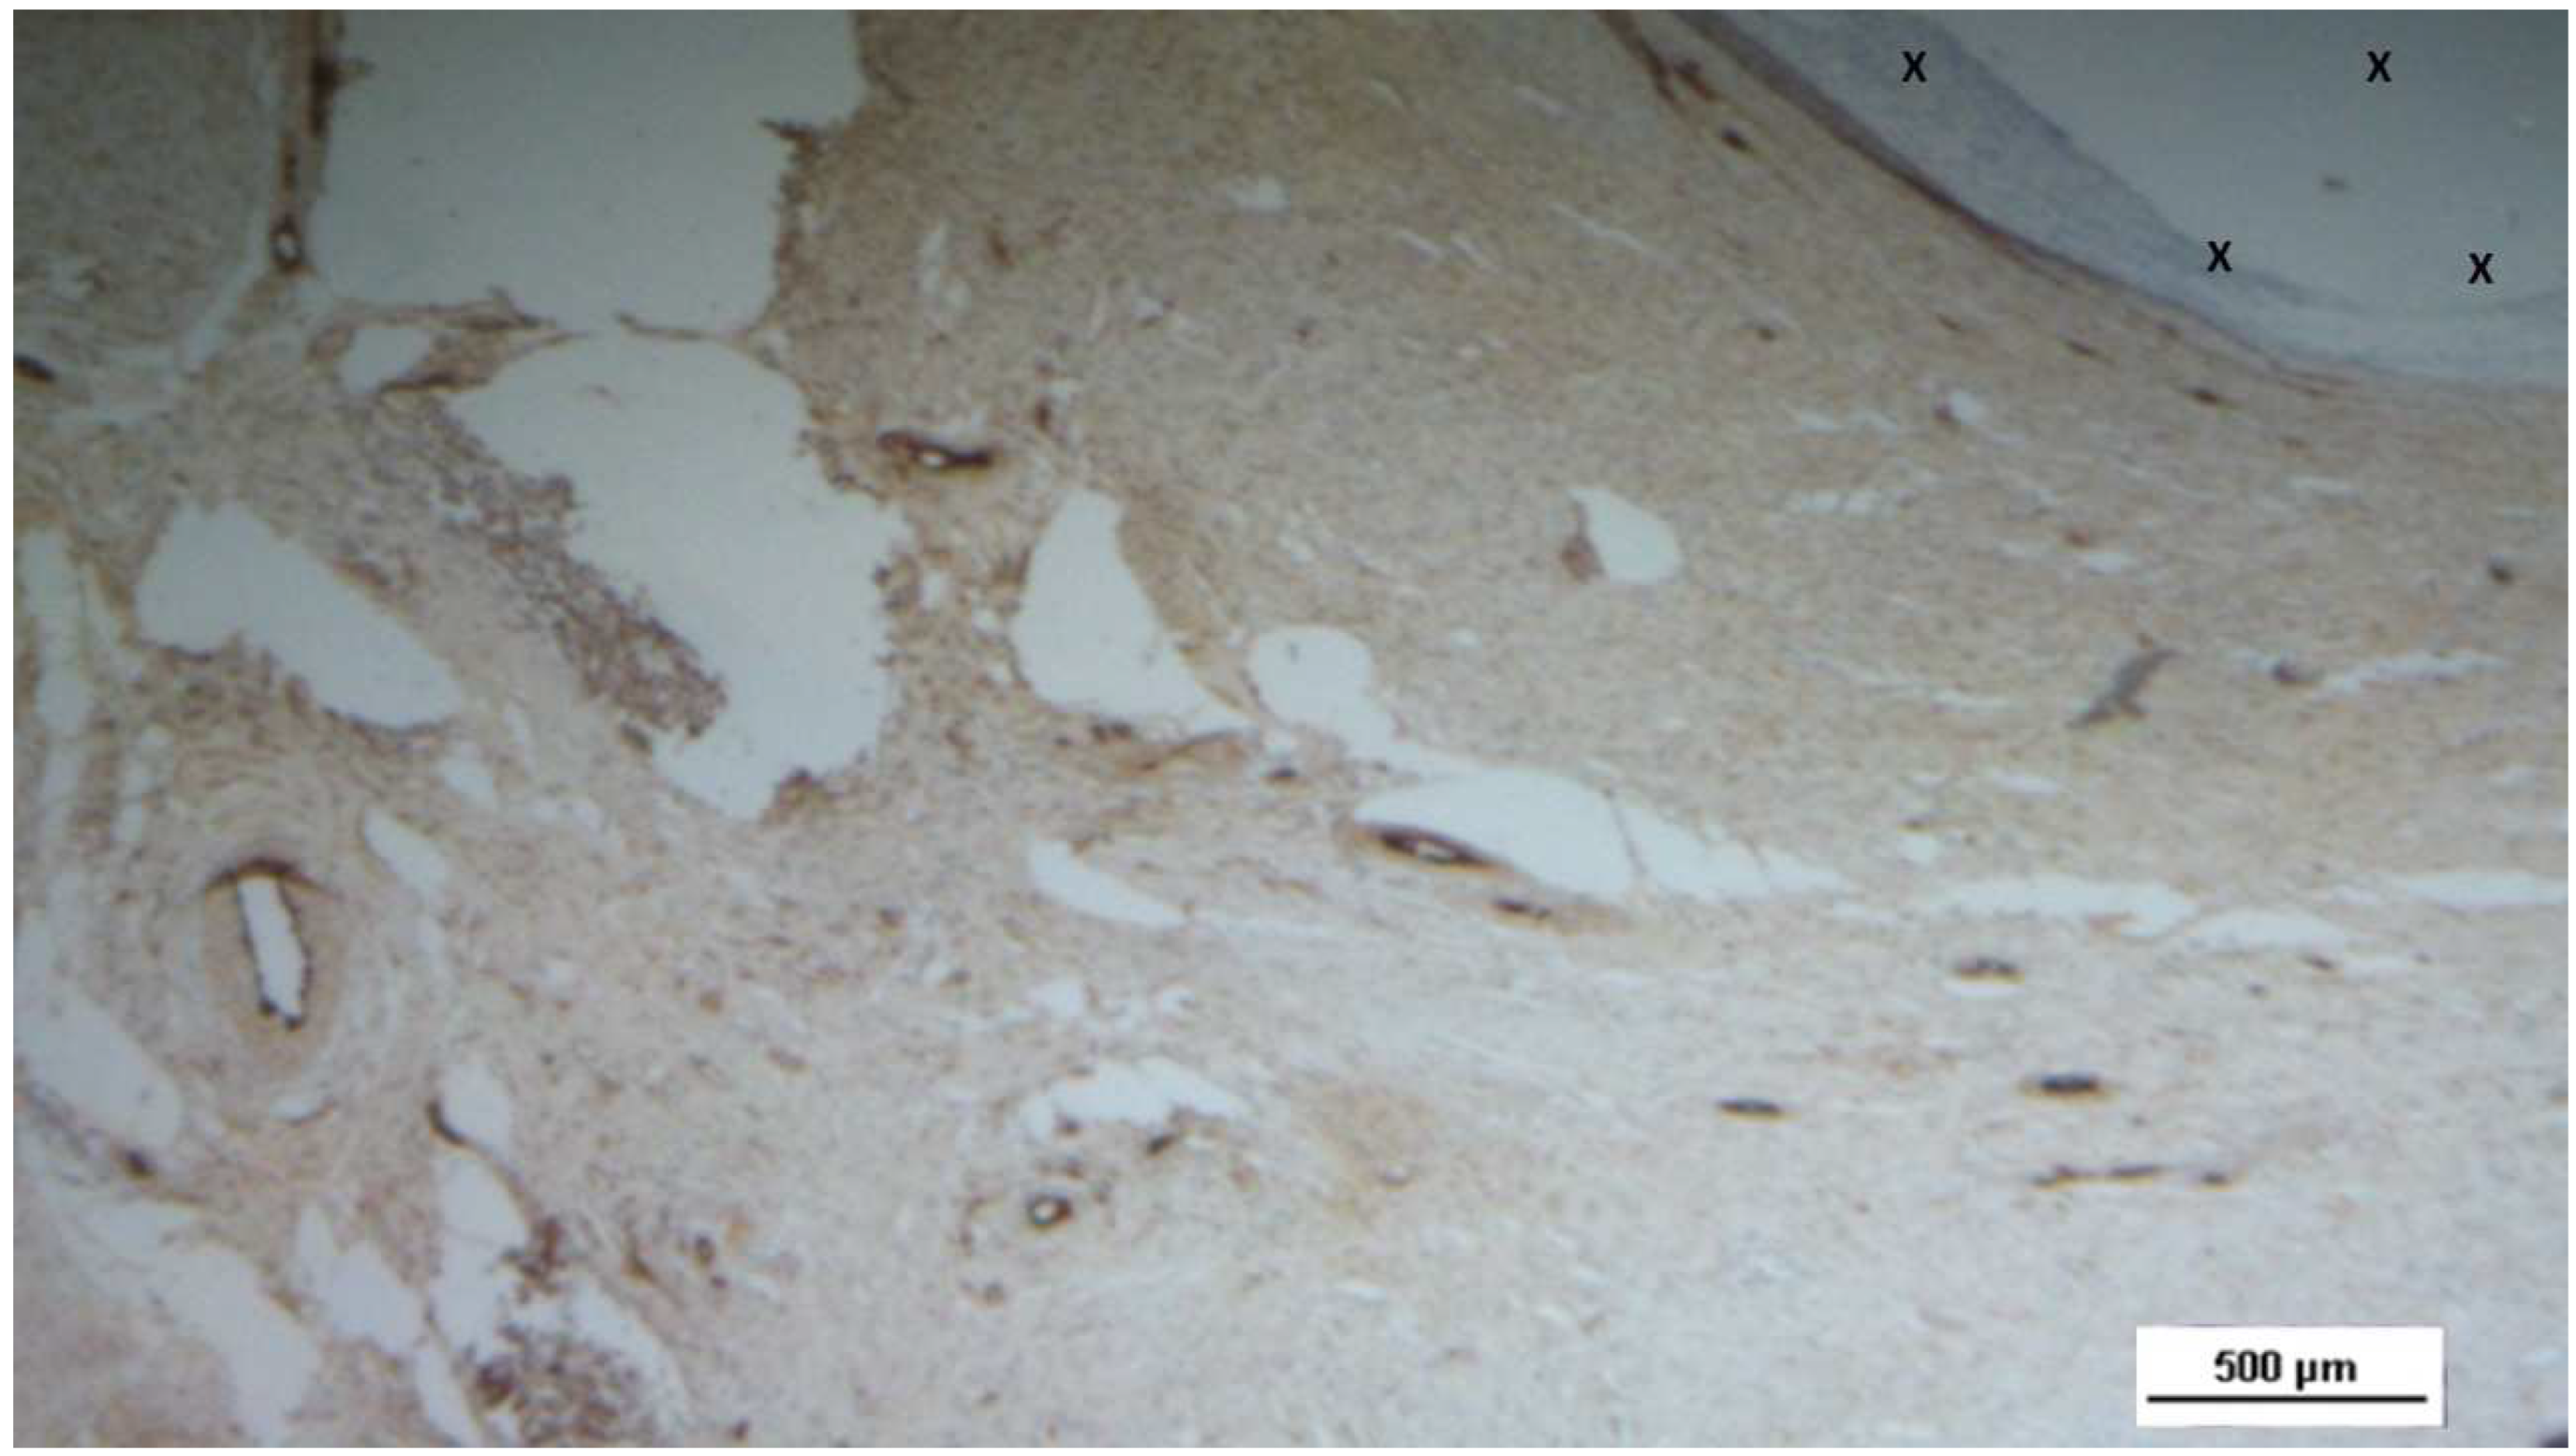

Figure 19. Biopsy specimen excised 7 months post-implantation (Long term - LT). Numerous NGF-positive elements in elongated bundles (brown staining) are visible near the structure of the 3D scaffold (X). NGF 100X.